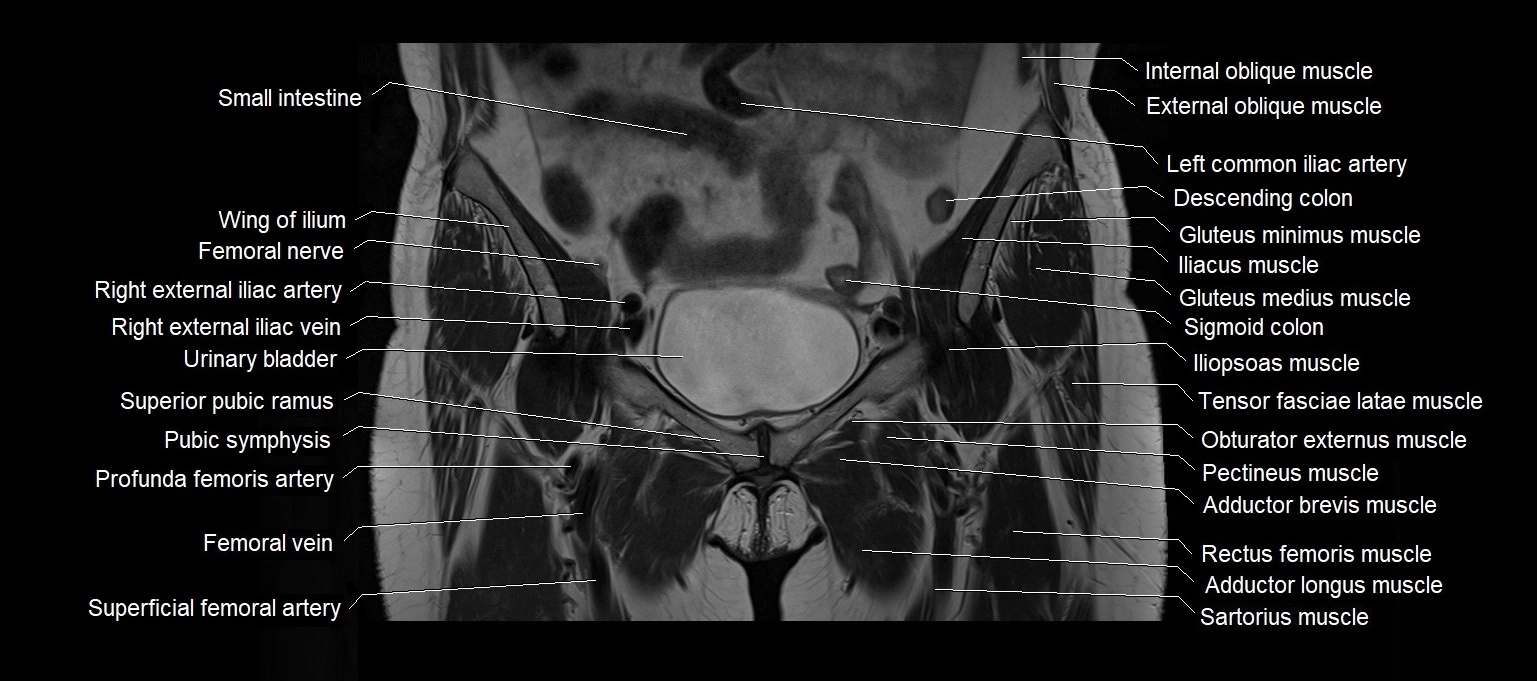

- Femoral vein

- Femoral artery

- Femoral nerve

- Deep femoral artery (profunda femoris)

- Superficial femoral artery

- Pubic symphysis

- Superior pubic ramus

- Obturator externus muscle

- Pectineus muscle

- Iliopsoas muscle

- Tensor fasciae latae muscle

- Iliotibial tract

- Sartorius muscle

- Rectus femoris muscle

- Gracilis muscle

- Adductor longus muscle

- Adductor brevis muscle

- Sigmoid colon